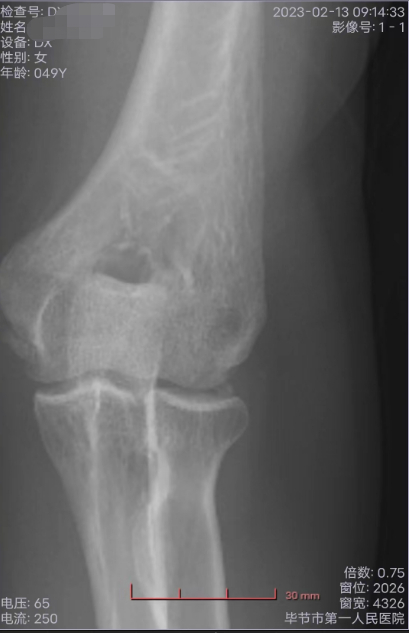

▲王某在毕节市第一人民医院进行检查

王某将两个儿子的遭遇归因为自己“无能”——2022年,她在意外摔跌后左肩胛骨骨折,手肘骨裂,又因为没有得到及时治疗,导致手肘缺血性坏死,并引发骨囊肿,急需手术,否则面临截肢风险。大儿子急于赚钱,就是为了帮她攒出手术费。